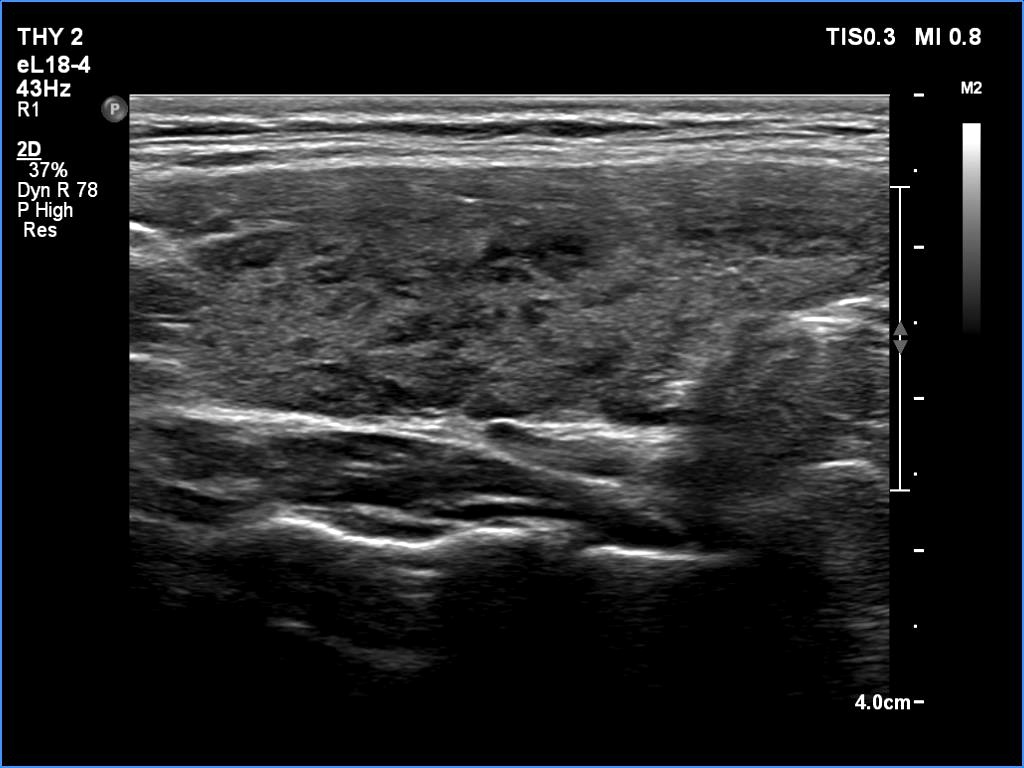

Third examination - seven years after the first examination (third row of images)

Clinical presentation: The patient hasn't been operated on, yet. She came to a repeat examination because of neck complaints, she felt pressure when lying down.

Palpation: a firm nodule in the left lobe.

Laboratory tests: TSH 1.70 mIU/L.

The dimensions of the nodule in the left lobe were 41x25x50 mm, width, depth, length, respectively, the volume of the lesion was 26.8 mL.

FNA resulted in follicular tumor.

Histopathology disclosed minimally invasive follicular cancer. The largest diameter was measured 55 mm. Both capsular and vascular invasions were found microscopically.

Comments. It is worth highlighting three changes. First, the nodule echogenicity has changed over time - from clearly hyperechoic to moderately hypoechoic. Secondly, the nodule substantially increased in size. This is the cause for the disappearance of the halo, due to the nodule growth, the capsule became invisible thin. Thirdly, the pattern of the intranodular hypoechoic parts has also changed.